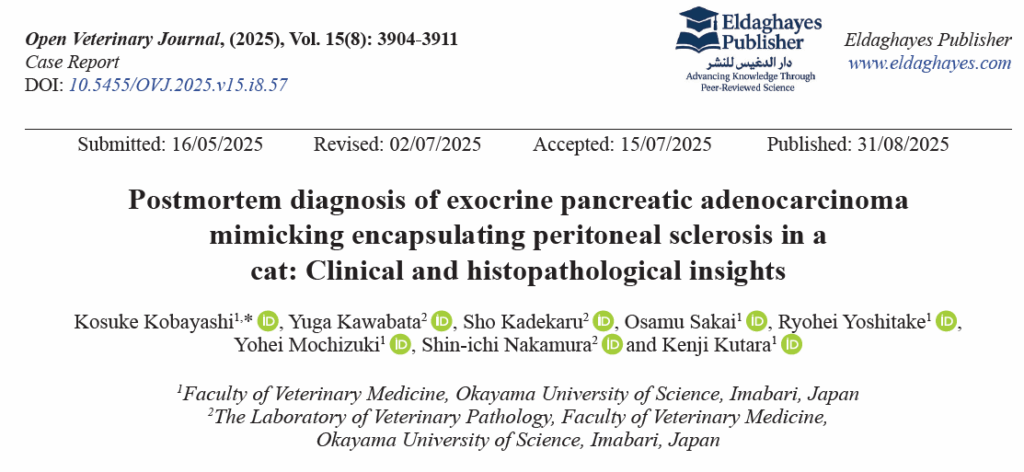

腹部X光显示腹腔透亮度增加和消化道影像重叠(下图)。

↑ (A)右侧位和(B)腹背位X光片。显示腹部严重膨隆,对比度普遍降低,提示腹水。观察到轻度气体滞留和肠道聚集(箭头)。